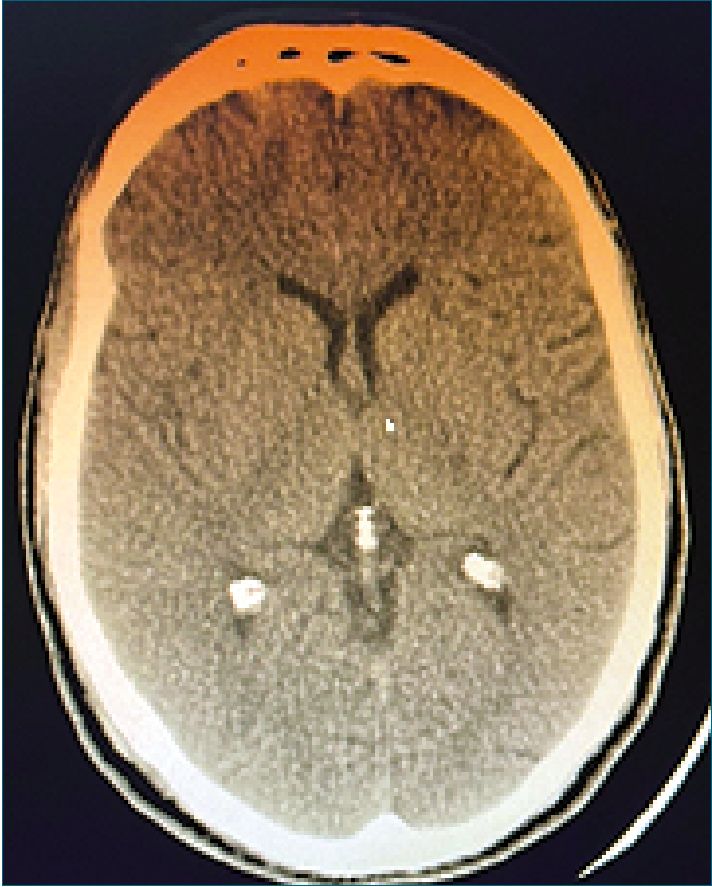

Extubación en block, paciente con ventilación espontánea con adecuado esfuerzo inspiratorio, cumpliendo órdenes. Paciente con tendencia al sueño, es trasladado a sala de recuperación anestésica. Inmediatamente, se revalora constatándose, hemiplejia izquierda, y parálisis facial central izquierda. Se realizó angioTAC cerebral y de vasos de cuello. Del informe se destaca: ausencia de signos tempranos de isquemia, ni áreas configuradas, sin hematomas del parénquima, hemorragia subaracnoidea ni sangrado intraventricular. Se identificó defecto en el relleno de carótida primitiva que podría corresponder a disección, y a nivel de cerebral media derecha en su sector M1 se observó defecto compatible con trombo embólico por contexto clínico del paciente (Figura 1).

Figura 1. AngioTAC posoperatorio inmediato de mediastinoscopia.